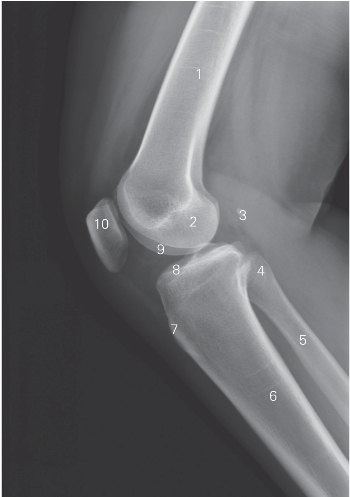

图7-7 膝关节侧位DR平片

1 股骨 femur 2 股骨内侧髁 medial condyle of femur

3 腓肠豆 fabella 4 腓骨头 fibular head

5 腓骨 fibula 6 胫骨 tibia

7 胫骨粗隆 tibial tuberosity 8 胫骨平台 tibial plateau

9 股骨外侧髁 lateral condyle of femur

10 髌骨 patella